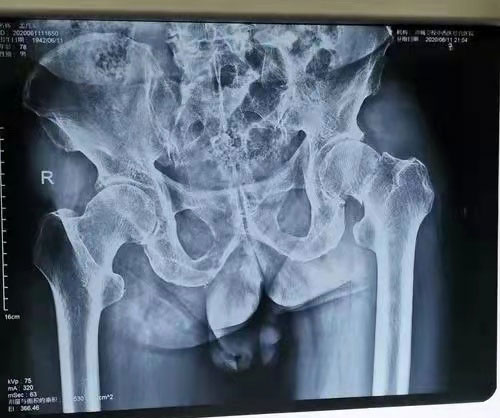

术前图片

“好得很,我的腿能弯能抬,已经下地在走廊来回走了好多次了”。近日,在来凤县人民医院骨伤科,做完手术后仅第二天,吴婆婆高兴地对医生说道。3月11日,71岁的吴婆婆在家中不慎摔倒,这一摔可不得了,老人家不仅无法行走,连翻身都成问题,只能平躺着。家属把吴婆婆送到中心县医院骨伤科就诊,经过拍片等检查,诊断为左股骨颈骨折,需要实施全髋关节置换手术。